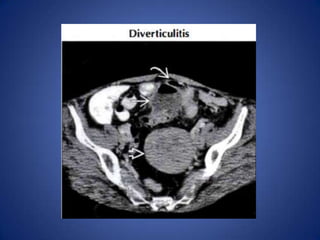

Diverticulitis

• Most common cause in middle-aged and

elderly

– Can affect patients as young as 25

• Usually long ( 10- 1 5 cm) segment of wall

thickening, luminal narrowing, pericolonic

infiltration

• Extraluminal collections of gas or fluid help

confirm diagnosis

Diverticulitis • Most commoncause in middle-aged and elderly – Can affect patients as young as 25 • Usually long ( 10- 1 5 cm) segment of wall thickening, luminal narrowing, pericolonic infiltration • Extraluminal collections of gas or fluid help confirm diagnosis